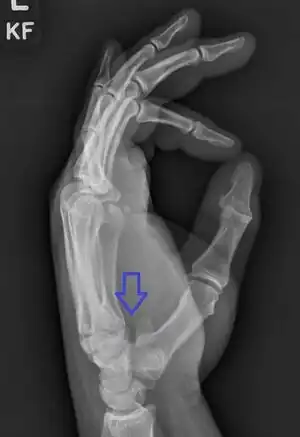

| Fracture through the hook of the hamate | |

The cause is typically injury during racket sports, baseball, or golf or a fall onto the hand.[1][2] Types include hook (most common) and body (proximal pole, medial tuberosity, sagittal oblique, and dorsal coronal).[1] Diagnosis is typically by X-rays, but may require special views such as a carpal tunnel or supinated oblique view; or a CT scan.[1]